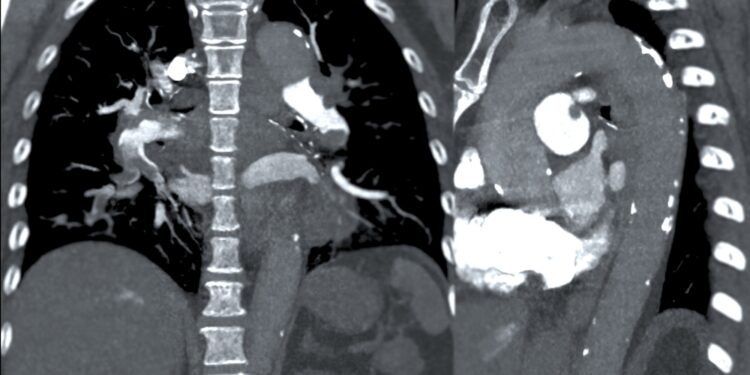

Dešinysis skilvelis yra viena iš keturių pagrindinių širdies ertmių, atliekanti svarbų vaidmenį kraujotakos procese – būtent ji varo deguonies stokojantį kraują į plaučius. Ši širdies dalis įsikūrusi apatiniame dešiniajame širdies kampe, po dešiniuoju prieširdžiu, priešingoje pusėje nei kairysis skilvelis.

Į dešinįjį prieširdį nuolat suplūsta deguonimi neaprūpintas kraujas iš viso organizmo. Tuomet jis keliauja per triburį vožtuvą ir patenka į dešinįjį skilvelį. Iš čia, dėl skilvelio susitraukimo, kraujas stumiamas per plautinį vožtuvą į plautinę arteriją ir nukreipiamas į plaučius, kur prisotinamas deguonimi.

Kai dešinioji širdies pusė pradeda silpnėti ir nebegali veiksmingai pumpuoti kraujo, kalbama apie dešinės pusės širdies nepakankamumą. Tokiu atveju kraujas užsistovi, atsiranda sąstovio požymių, todėl ši būklė dar vadinama staziniu širdies nepakankamumu.